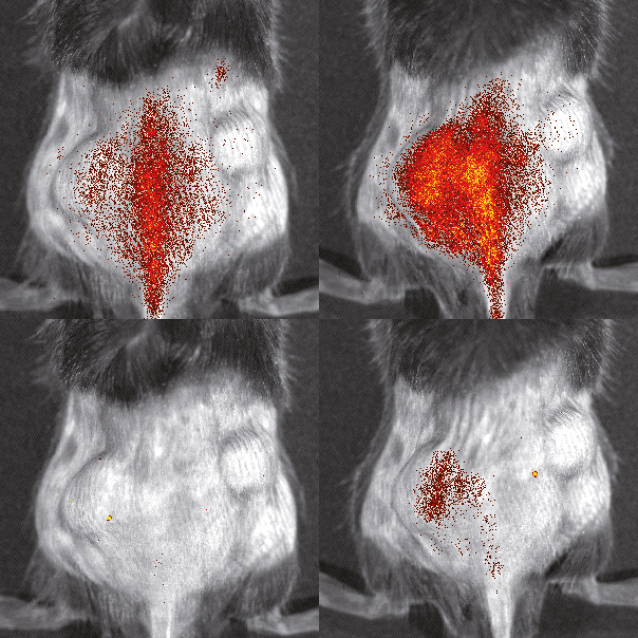

Bildgebung von markierten Monozyten während eines Herzinfarkts© EIMI/M. Schäfers Combining myeloid precursor immortalization, genome editing and genetic reporter systems for imaging of monocyte trafficking in inflammation and ischemia

Förderkennzeichen: DA 1064/3-1 | DFG EinzelförderungMonitoring molecular mechanisms of monocyte migration during inflammatory processes in vivo

Projektleitung: Michael Schäfers (EIMI), Johannes Roth

Projektlaufzeit: 07/2013 - 06/2015

Förderkennzeichen: EXC 1003 FF-2013-24 | DFG Exzellenzcluster "Cells in Motion"Regulation adulter Neurogenese durch inflammatorische Prozesse